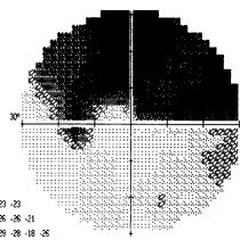

Abbildung 2: Typischer Gesichtsfelddefekt bei Glaukom

Abbildungen 4: Progredienter Gesichtsfeldzerfall beim Glaukom